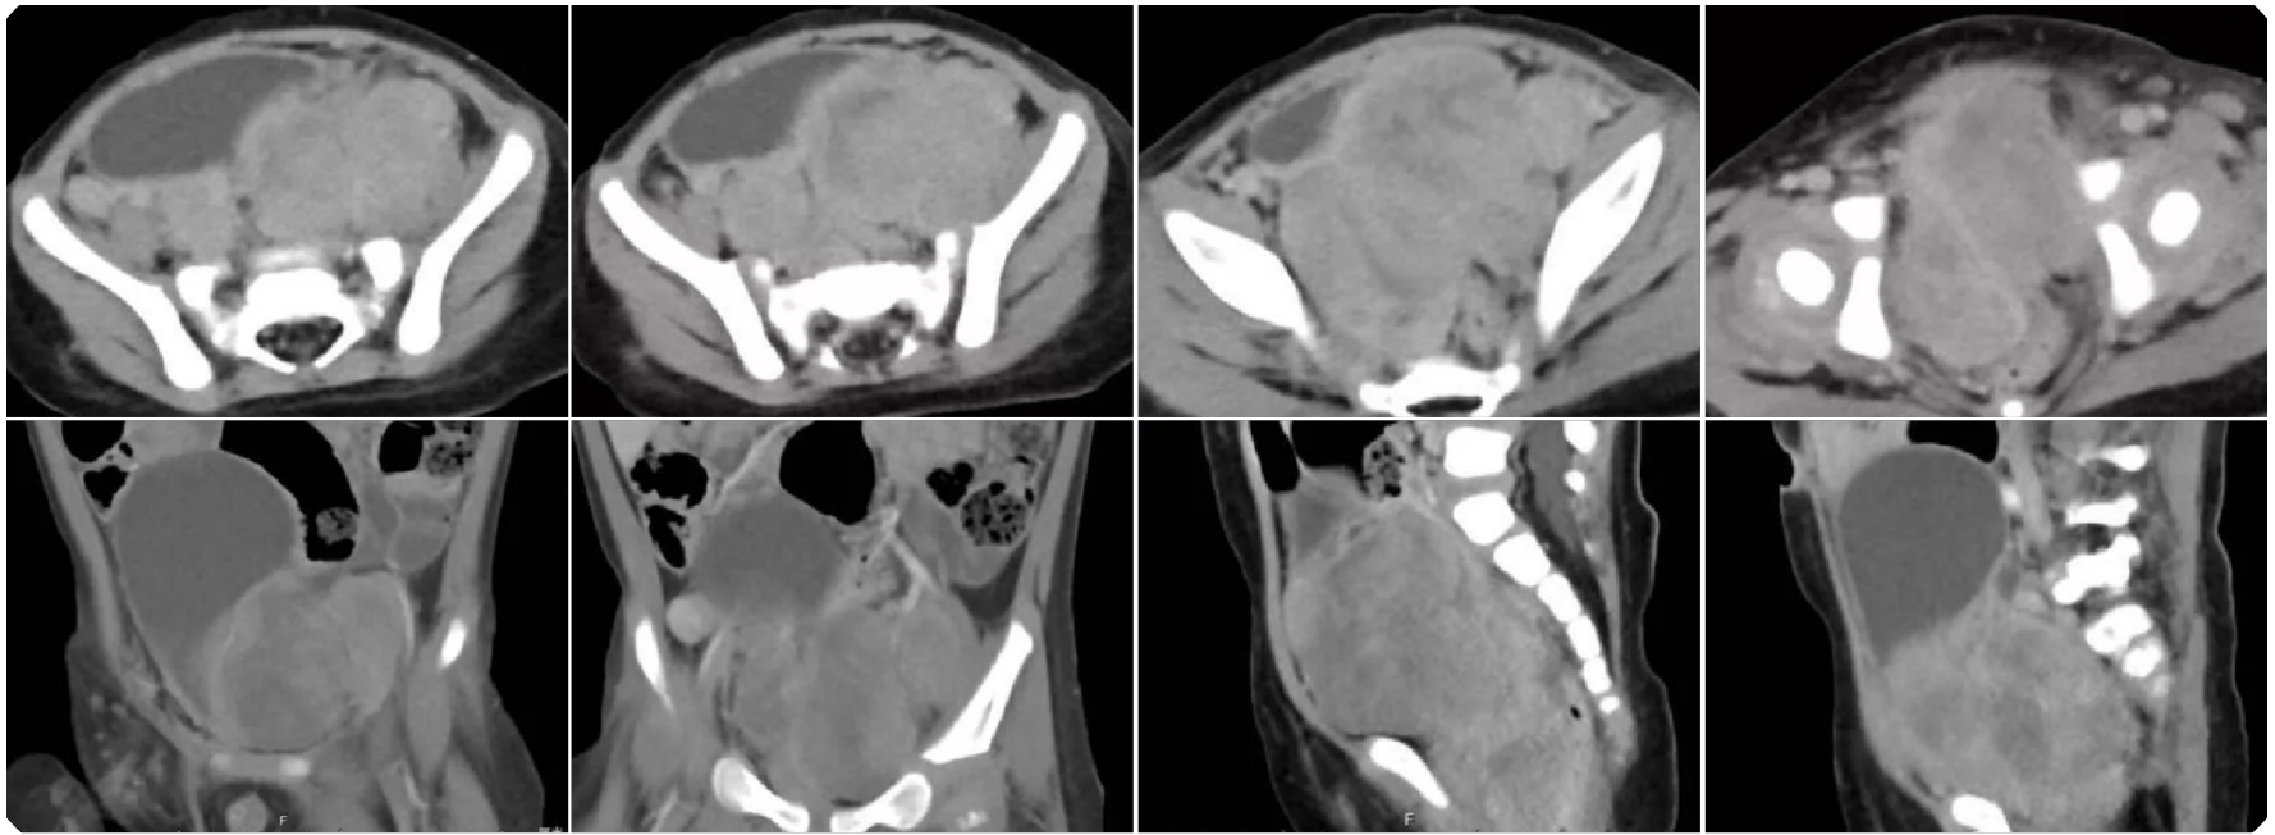

e6b157565c20beba067400577029f65f.png 病例 7:腹膜后(血管外)平滑肉瘤1例

增强CT(横、冠、矢状位)(a、b) 增强扫描动脉期与增强扫描静脉期;(c、d) 冠状位与矢状位影像。腹膜后单发肿瘤,体积较大,边缘规则的软组织肿块,有包膜,内密度不均匀,多发低密度灶;增强扫描,不均匀轻中度强化,内有不强化中心坏死灶与囊变区,门脉期较动脉期强化明显。增强扫描呈轻度渐进性强化,没有明显钙化灶,周围无明显肿大淋巴结。